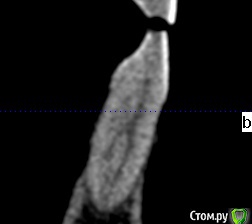

shurkne Опубликовано 10 мая, 2015 Поделиться Опубликовано 10 мая, 2015 (изменено) Здравствуйте!Зуб 1.3..есть небольшое углубление видимо вызванное стиранием.Выпил чая горячего,зуб легонько заныл в месте стирания и продолжает легонько поднывать.Подскажите что с зубом? и сколько там каналов?) Изменено 10 мая, 2015 пользователем shurkne Ссылка на комментарий

Гарриевич Опубликовано 10 мая, 2015 Поделиться Опубликовано 10 мая, 2015 Канала дваНадо холодом проверить зуб Ссылка на комментарий

shurkne Опубликовано 12 мая, 2015 Автор Поделиться Опубликовано 12 мая, 2015 (изменено) Четко 3.1 поднывает.(в первом сообщении ощибся с нумерацией)......выпил чая горячего и заныл немного....больше на температурные раздражители не реагирует никак....щас периодически немного беспокоит само место стирания Изменено 12 мая, 2015 пользователем shurkne Ссылка на комментарий